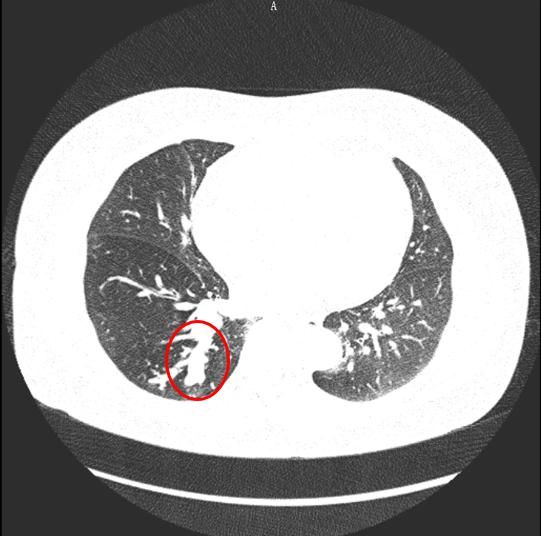

杨红(化名)肺部CT影像,红圈内的白色部分是异物刺激气管壁后长出的肉芽肿。